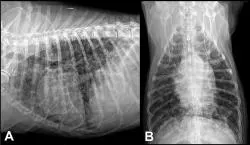

Figure 1: Right lateral (A) and ventrodorsal (B) radiographic projections of the thorax of a dog presenting with acute respiratory distress. An alveolar lung pattern is present in the right cranial, middle, and caudal lung lobes, a pattern consistent with aspiration pneumonia. Megaesophagus is present (black arrows), likely leading to chronic regurgitation and secondary aspiration.

Pulmonary parenchymal disorders, such as pneumonia (Figure 1), edema (cardiogenic or noncardiogenic), pulmonary contusions, interstitial lung disease, and neoplastic or fungal infiltration (Figure 2), can lead to both inspiratory and expiratory difficulty. The presence of heart murmurs, gallops, or arrhythmias may suggest underlying heart disease but not necessarily congestive heart failure.